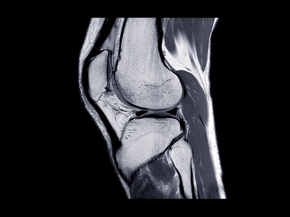

First, your surgeon will obtain x-rays to evaluate your joint and determine whether or not you're a candidate for cartilage restoration surgery. Advanced imaging, such as an MRI, is usually necessary to assess cartilage defects and develop a treatment plan.